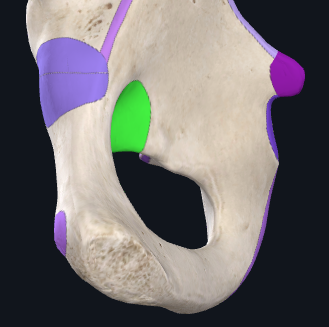

Bony lands marks?

1) Inferior ischial ramus - combine with the inferior pubic ramus to form the ischiopubic ramus.

2) Ischial tuberosities - posteroinferior aspect of the ischium. When sitting, out these tuberosities support the body’s weight.

3) Ischial spine - sharp posteromedial projection

Ligaments associated with the ischium

1) Sacrospinous ligament - ischial spine to the sacrum, creating the greater sciatic foramen. Sciatic nerve enters through here.

2) Sacrotuberous ligament - ischial tuberosity to the sacrum, formin the lesser sciatic foramen.